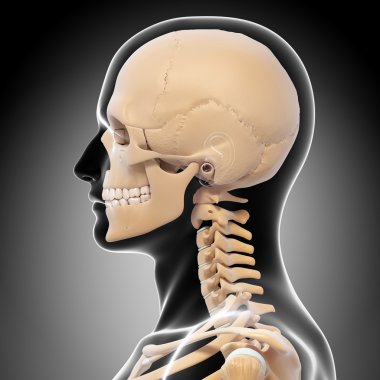

iskelet adam yan görünüm baş ve sinir sistemi